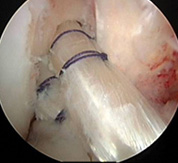

再建直後